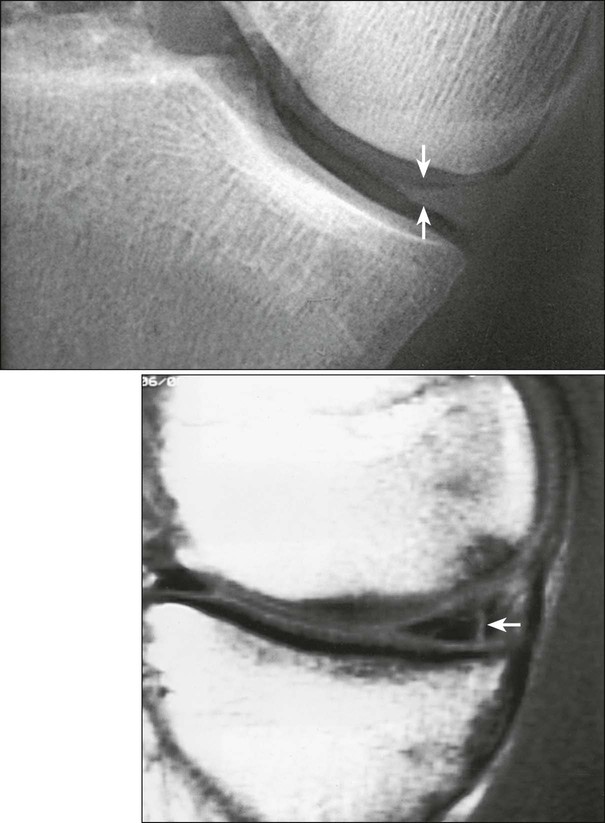

Arthrography of the shoulder is performed primarily for the evaluation of partial or complete tears in the rotator cuff or glenoid labrum, persistent pain or weakness, and frozen shoulder. A single-contrast technique (Fig. 12-4) or a double-contrast technique (Fig. 12-5) may be used.

For a single-contrast arthrogram (Fig. 12-6), approximately 10 to 12 mL of positive contrast medium is injected into the shoulder. For double-contrast examinations, approximately 3 to 4 mL of positive contrast medium and 10 to 12 mL of air are injected into the shoulder.